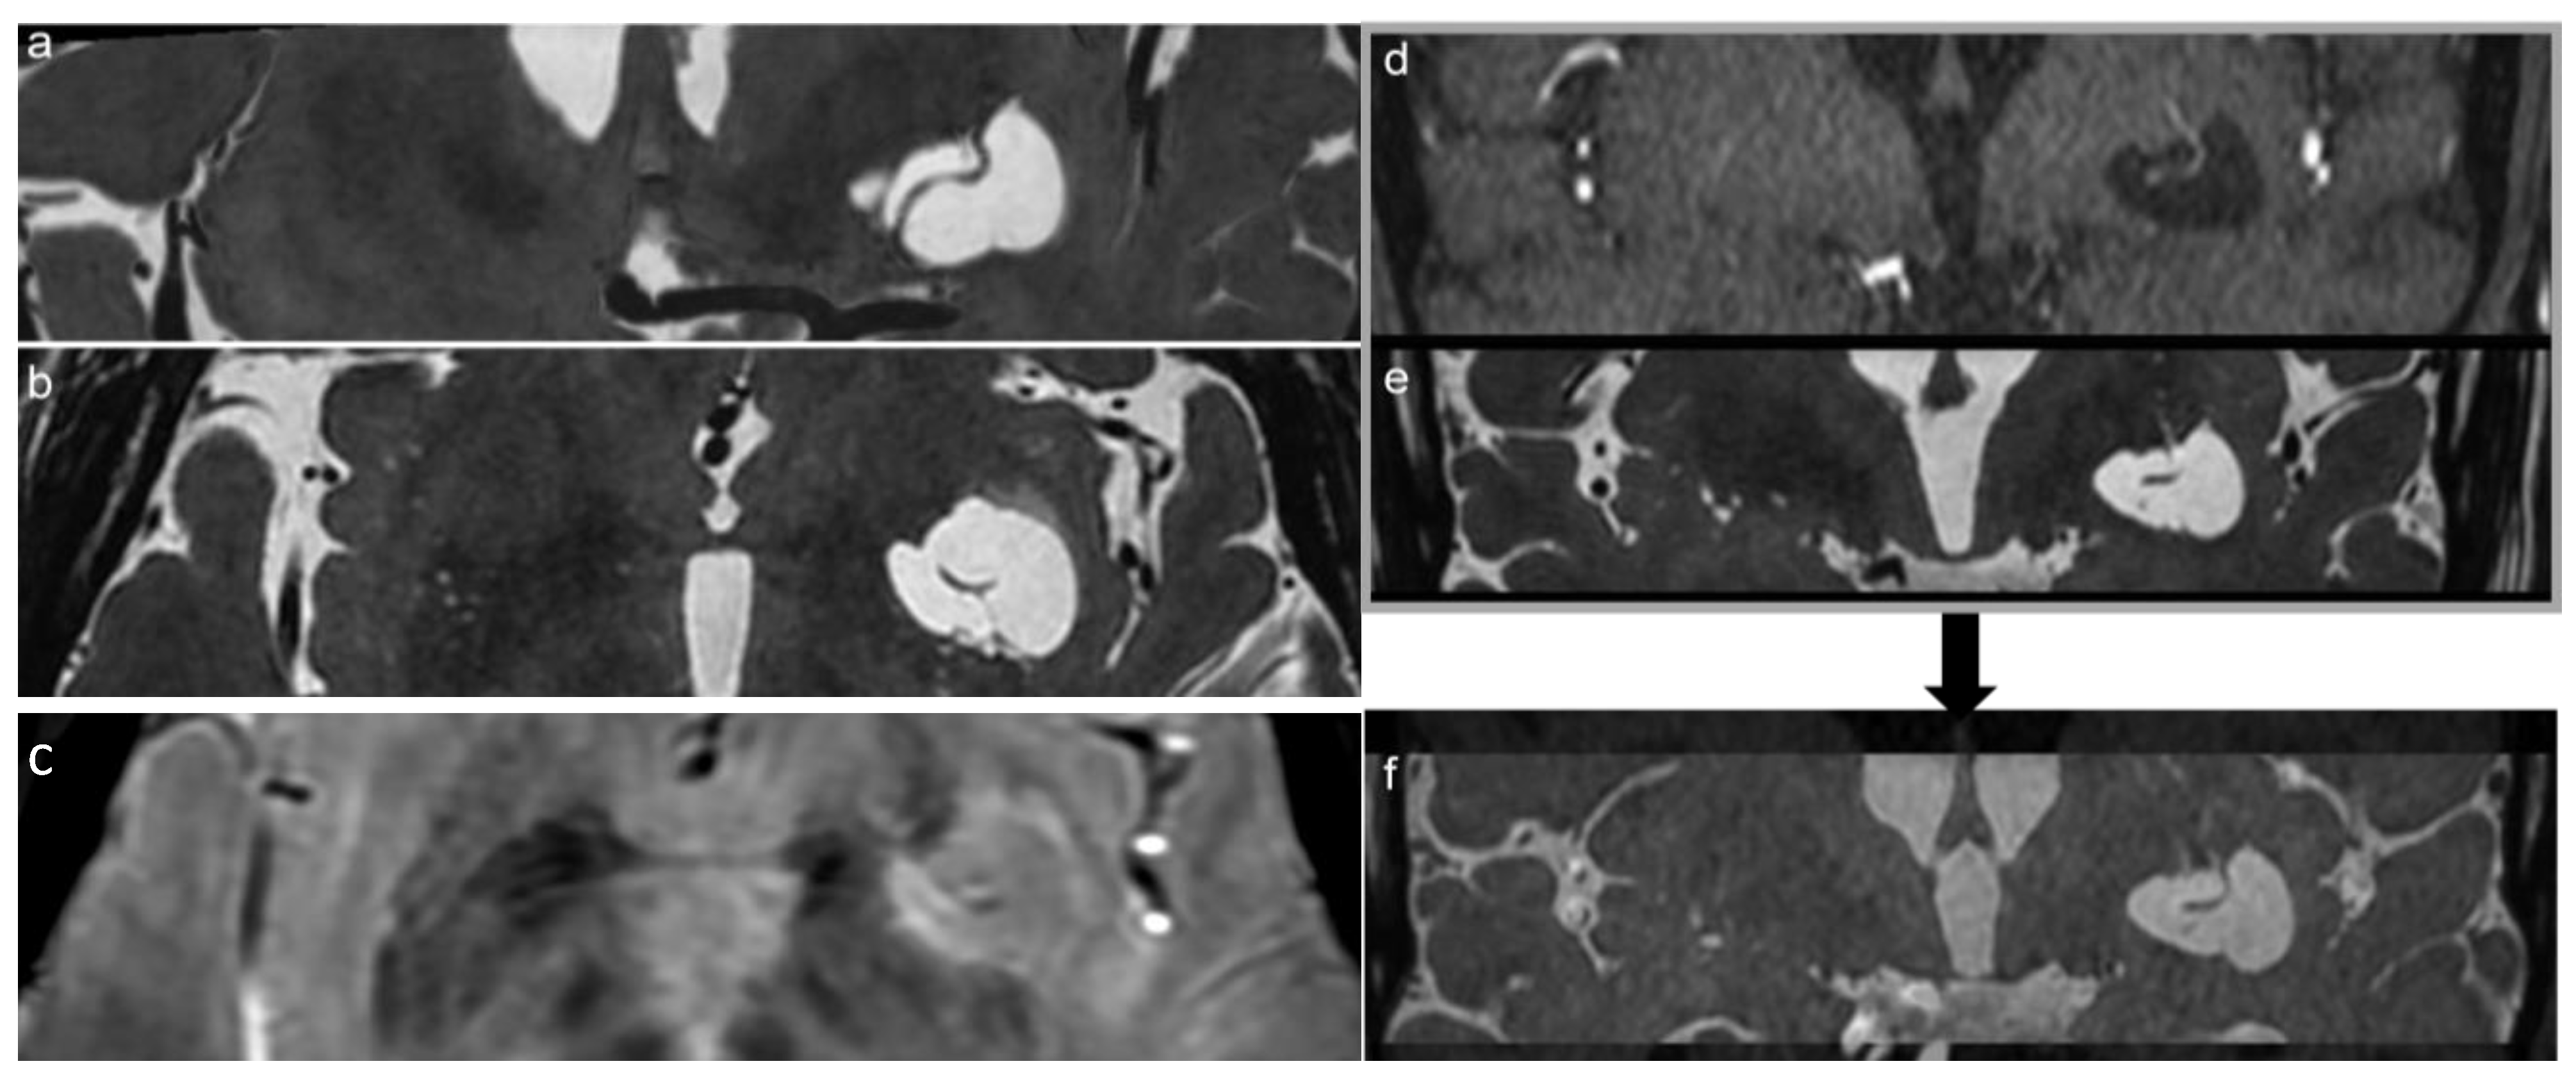

The MRI study confirmed the up-mentioned CT features, showing a cystic-like parenchymal area 3 × 2.8 cm in diameter and 3.0 cm3 volume, isointense to the CSF in all sequences, partially surrounded by a close thin area of gliosis, no contrast enhancement, but with better evidence of the linear structure within the area, compressing the neighboring brain structures (Figure 1). The 3D CISS sequence showed the “ribbon-like” structure inside the cystic-like lesion that the fusion image (CISS + TOF) confirmed to be a perforating artery with a redundant course (Figure 2). DWI and apparent diffusion coefficient (ADC) maps showed no signal restriction (not shown). Based on radiological studies, the diagnosis suggested a GTPVS.

Figure 2.

Coronal and axial reconstruction of the 3D CISS sequence shows the irregular shape of the GTPVS with multiple linear vascular-like images inside (a,b). (c) 3D SWAN on the axial plane better demonstrates a linear vascular structure within the GTPVS. (f) notes the clearer image of the vessel inside the GTPVS resulting from the fusion of d-TOF and e-CISS images. (d) Coronal TOF and (e) coronal CISS images are fused together in figure (f): notes the clearer image of the vessel inside the GTPVS resulting in the fused image.

In this study, in agreement with previous reports, we underline the essential role of the 3D CISS sequence to enable the estimation of brain water content and to evaluate fluid-filled spaces and their 3D observation, clearly revealing the fine morphological features of GTPVSs. Moreover, GTPVSs in the basal ganglia, as in our case, are described in the literature as irregularly sized, with some parts dilated and others markedly narrowed, and arteries seen within them are identified as perforating arteries. Sometimes GTPVSs communicate with CSF in the basal cistern crossing the fiber tracts of the internal capsule [11]. Type 1 GTPVSs have two histologic components: a vessel traversing the brain from the pia and a fluid-filled space surrounding the vessel [23]. The recently described characteristic “linear sign” was observed also in our study, in both 3D CISS and TOF images, indicating the presence of GTPV-traversing vessels [3] being thin straight or slightly curved lines cutting across cystic lesions. Particularly, in the case of a PVS ≥ 5 mm, a 3D CISS sequence is recommended to carefully identify thin linear low signal structures within the cystic lesions [3,23]. Using TOF, we confirm previous observations that lenticulostriate arteries are an important source of “linear sign”; moreover, it gives better specificity and accuracy than T2w sequences alone [23]. We use TOF/3D CISS fusion images to increase the MRI sensibility of recognizing the two different GTPVS histological components [11] (Figure 2).